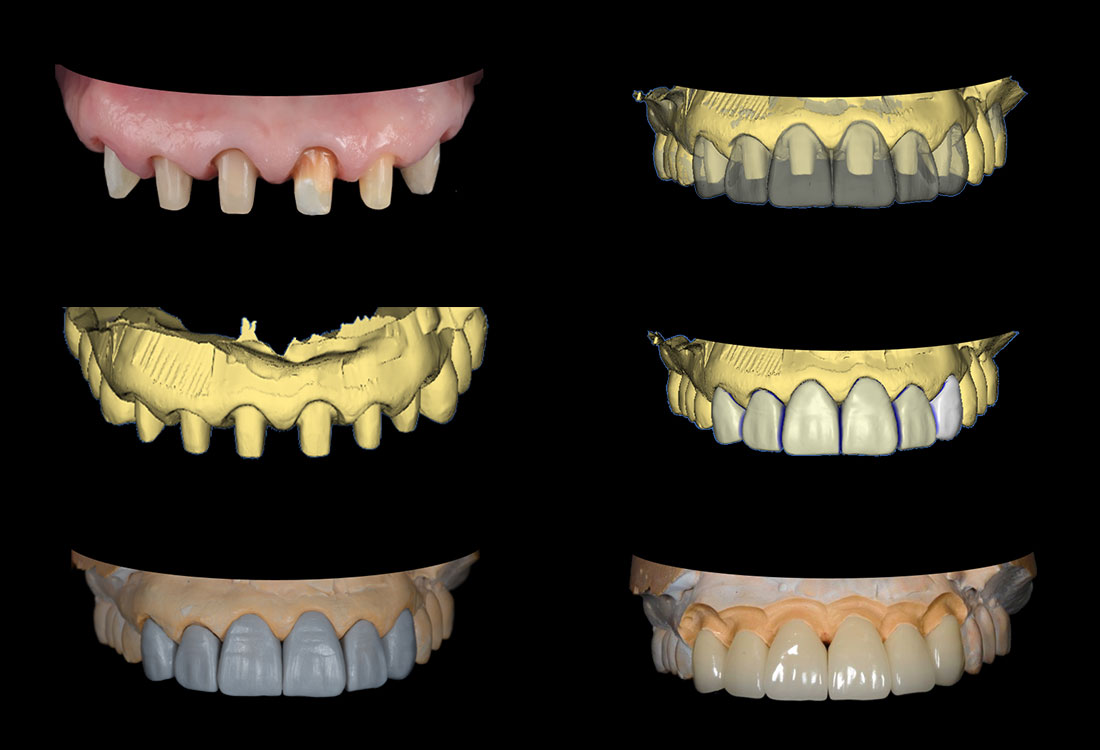

治療症例 Case3

Treatment cases

治療内容

模型を作成して最終的な形を模索します。

土台になる歯の形を整えて最終的な形の模型を作ります。